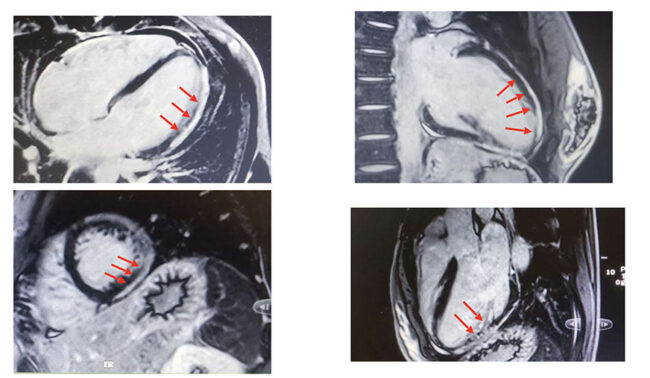

Lo sport diventa rifugio, forza, identità. Poi arriva la corsa in montagna, in solitaria. Giulia non vinceva: dominava. Le avversarie gareggiavano per il secondo posto. Ma qualcosa la spinge a chiedere una valutazione. Non si sentiva bene? L’ECG mostra un pattern familiare: onde T sempre più negative nelle derivazioni antero-laterali, perdita di vettori in V4-V6. Un’evoluzione sospetta (Figura 1). Ne abbiamo già visti, troppi, così. Nel 2023, le prime aritmie ventricolari. Poi tre sincopi da sforzo. La prima durante una gara al sole: si ferma, cade a terra. I test iniziali (Holter, ecocardiogramma) non mostrano nulla. Nessuna seduta di allenamento monitorata. Si continua a valutare atlete ed atleti in modo “statico”: ogni anno fa storia a sé. Nulla di più pericoloso. Le sincopi si ripetono. Dopo l’ultima va in Pronto soccorso. L’ECG è peggiorato, aritmie polimorfe anche a riposo. Finalmente si prescrive una risonanza magnetica con contrasto. Ma è negativa. Non ci convince. La ripetiamo: il quadro è devastante. Ventricolo sinistro moderatamente dilatato, funzione sistolica lievemente ridotta, parete laterale assottigliata e ipocinetica. Anche il ventricolo destro presenta una focale acinesia. E ovunque, un bianco che non consola come la neve che Giulia è abituata a vedere durante le sue salite invernali. È un bianco che spaventa, è il bianco del gadolinio che si accumula a disegnare la malattia. Diagnosi: cardiomiopatia aritmogena biventricolare. L’ECG non mentiva. Rivedendo la prima risonanza, scopriamo che il quadro era già presente.

Solo non era stato riconosciuto. Un errore interpretativo. Negli ultimi anni sono troppi i centri che si improvvisano esperti di risonanza magnetica cardiaca, serve prudenza, esperienza, rigore. Questa approssimazione spaventa. Le cardiomiopatie aritmogene sono malattie del miocardio, con alterazioni strutturali permanenti. Possono essere genetiche o acquisite. Quella di Giulia è cicatriziale, con fibrosi non ischemica che espone a gravi aritmie. La diagnosi arriva in un momento cruciale: Giulia ha appena firmato il contratto della vita. È venerdì. Prepariamo il colloquio, consapevoli che stiamo per dirle che la sua corsa è finita.